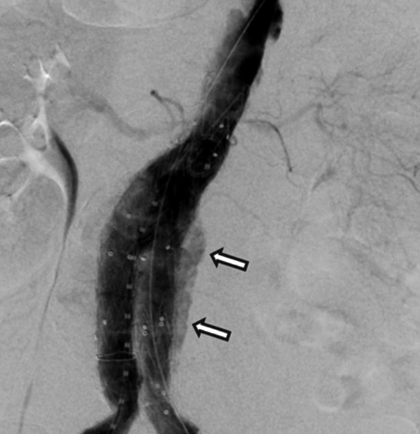

En la angiografía final se identificó flujo de contraste a través del cuerpo de la endoprótesis (endofuga tipo IV) que rellenaba el saco aneurismático (Figura 1), siendo diagnosticado al descartar otras endofugas (Ia, Ib, II y III) y evidenciar un tiempo de activación de coagulación mayor a 400 s. Se decidió manejo conservador y revertir la heparinización con protamina IV.